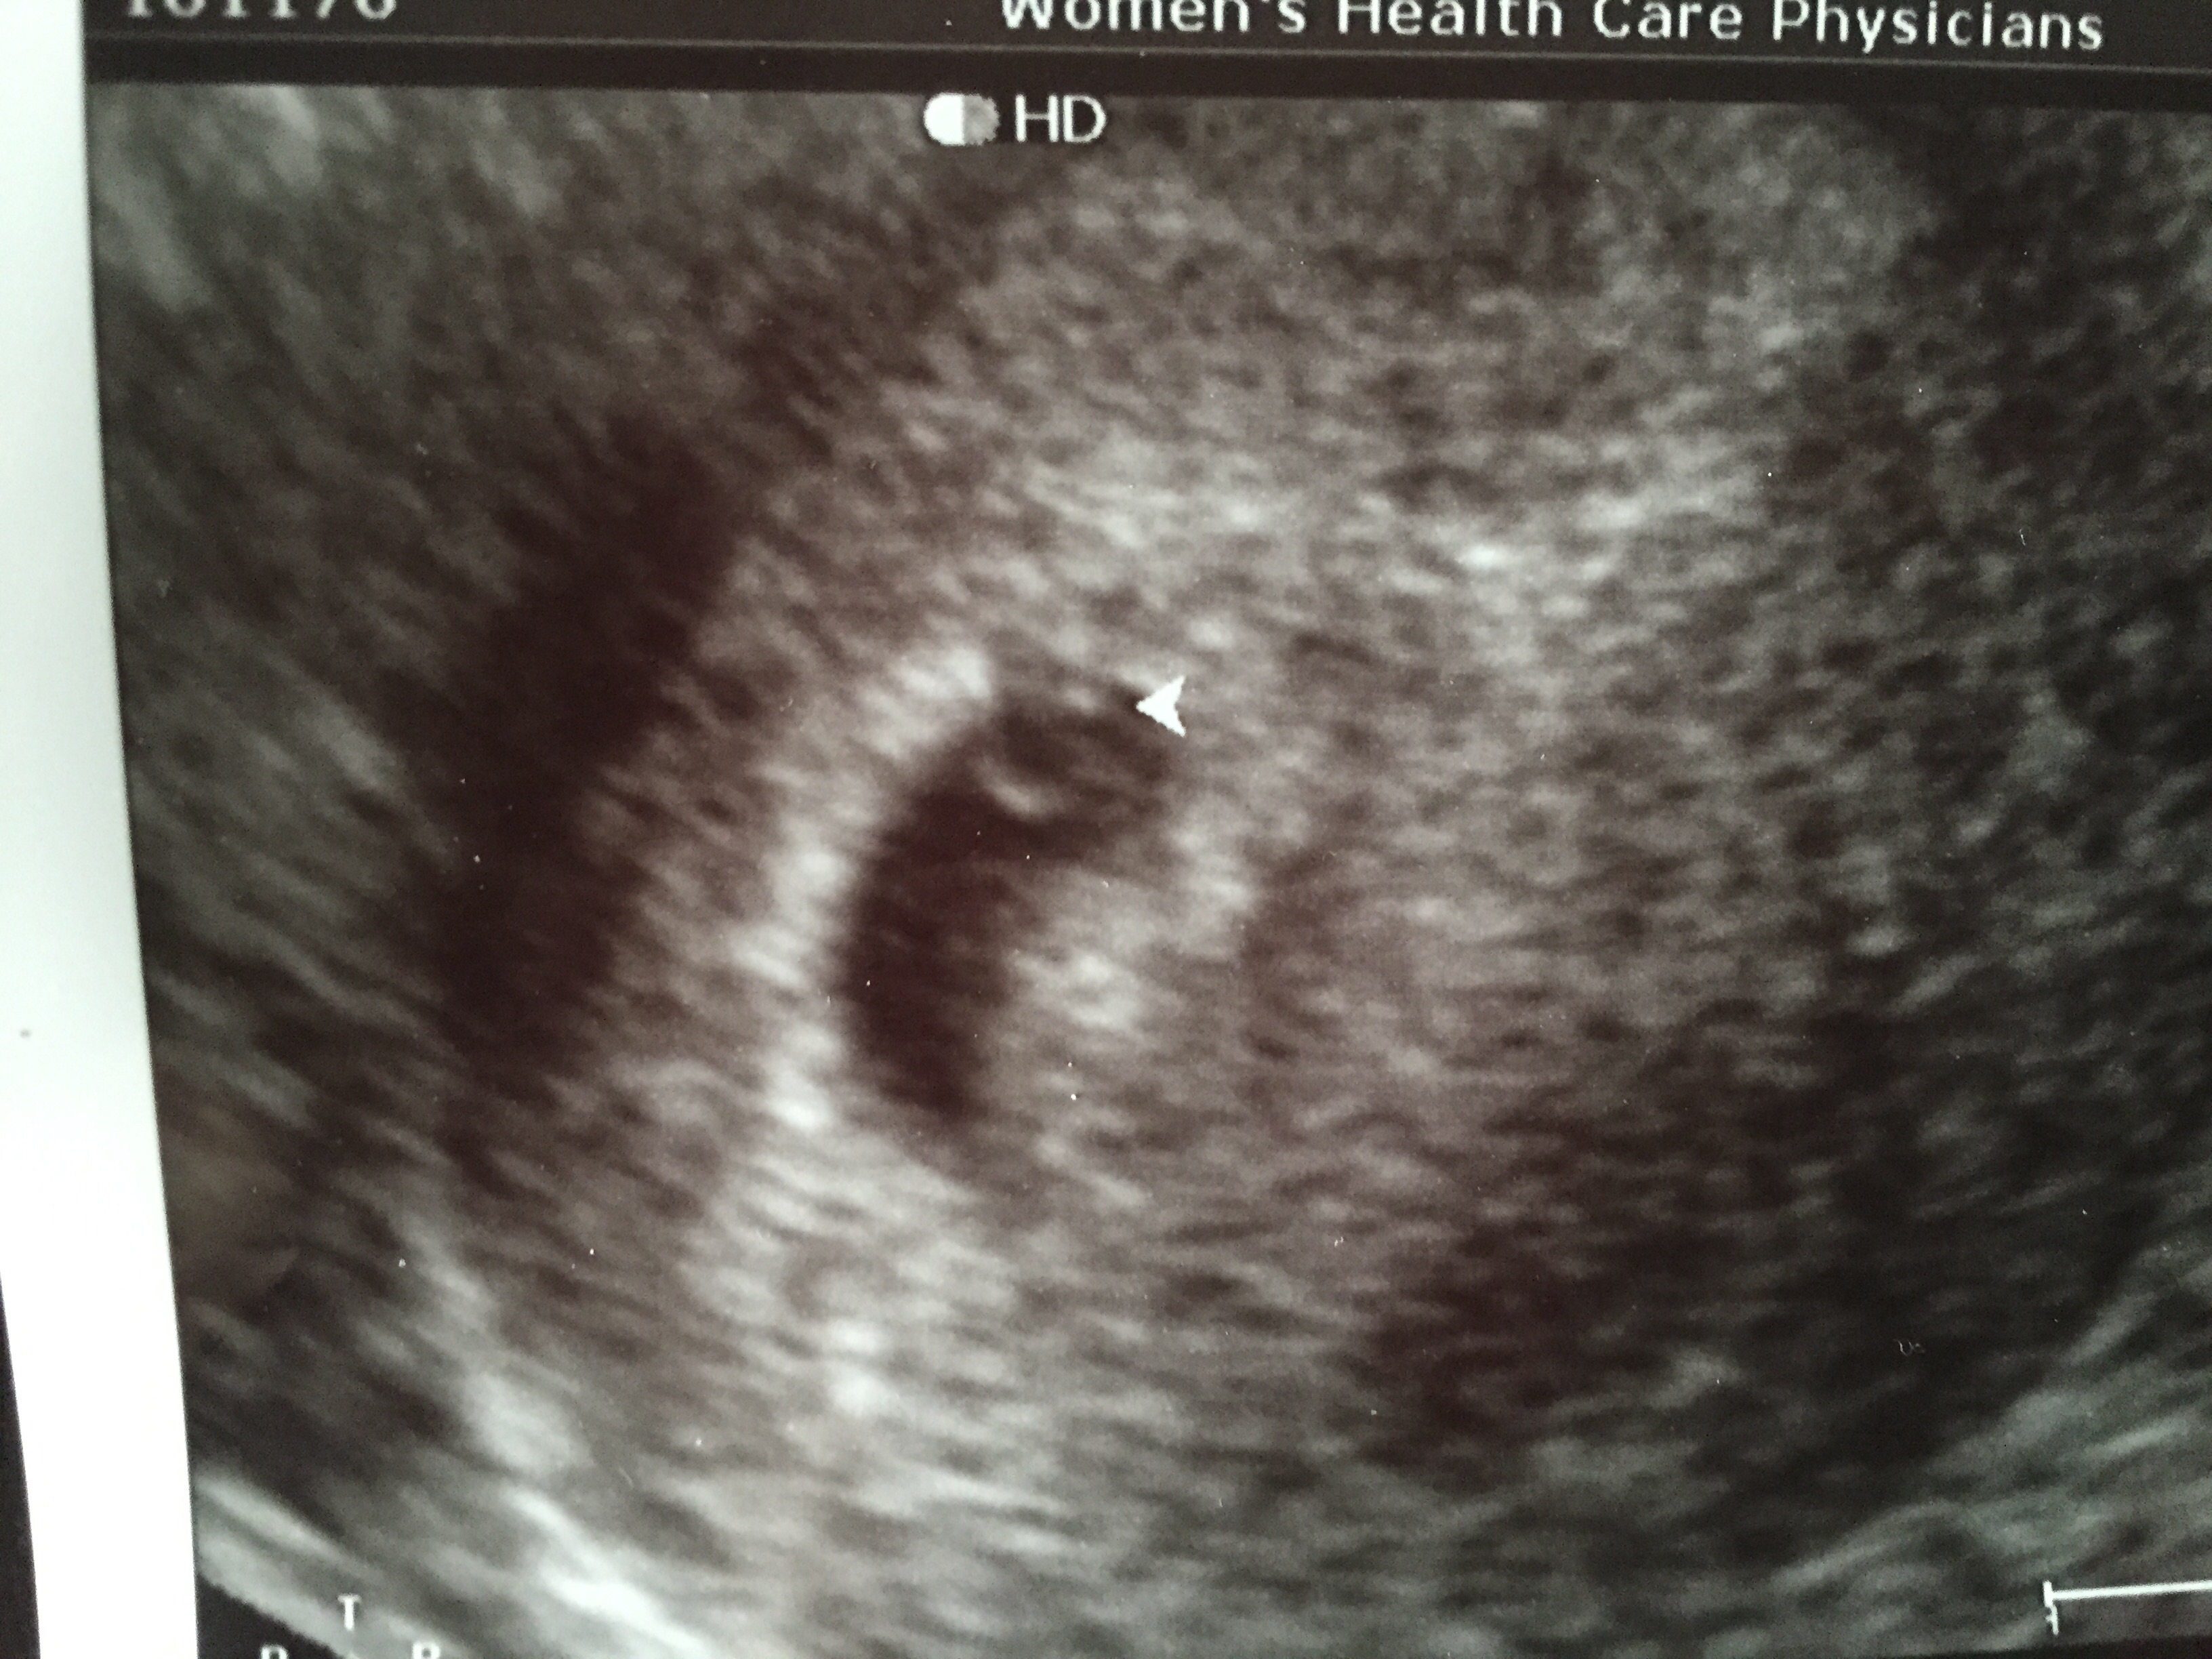

Our little one today! 6w1d

108HB